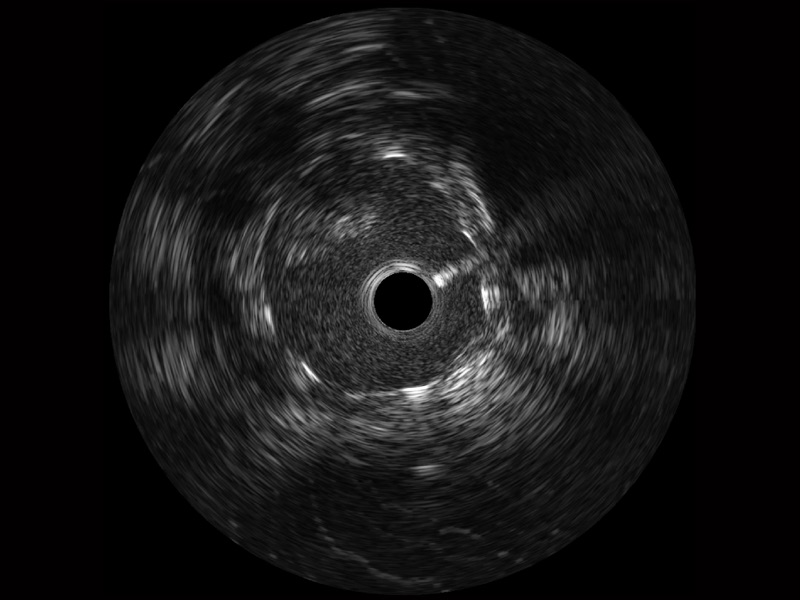

传统IVUS图像

对比传统IVUS导管成像,米兰官方网站宽频IVUS图像的近场支架梁显影更细腻,远场中膜外血管仍清晰可辨,兼顾远中近,兼顾分辨力与穿透深度